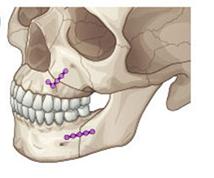

¼ö¼ú±³Á¤

¼ºÀο¡¼ °ñ°ÝÀûÀÎ ¹®Á¦(ÁÖ°ÆÅÎ, ¹«ÅÎ, ¾È¸éºñ´ëĪ µî)¸¦ ÇØ°áÇϰíÀÚ ÇÒ °æ¿ì ±³Á¤°ú ¼ö¼úÀ» µ¿½Ã¿¡ ÇÊ¿ä·Î ÇÏ°Ô µË´Ï´Ù(±×¸²6). ÀÌ °æ¿ì ÀϹÝÀûÀ¸·Î ¼ö¼úÀ» À§ÇÑ Áغñ(¼úÀü±³Á¤) - ¼ö¼ú - ¼ö¼ú ÈÄ ±³ÇÕÈ®¸³À» À§ÇÑ ±³Á¤(¼úÈı³Á¤)ÀÇ °úÁ¤À» °ÅÄ¡°Ô µÇ´Âµ¥ Åë»óÀûÀ¸·Î 2³â ÀÌ»óÀÇ ±â°£ÀÌ ÇÊ¿äÇÕ´Ï´Ù.

| | ±×¸²6 |